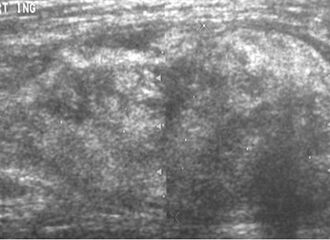

قد لا يكون التصوير بالموجات فوق الصوتية قادراً على التمييز بين الغرن الشحي والورم الشحمي الحميد، وبالتالي، فإن التصوير بالرنين المغناطيسي هو التصوير الأولي المفضل.[4]

Ultrasonography of a liposarcoma mimicking a lipoma. A homogeneous hypoechoic mass presenting with the same appearance of lipoma. It was clinically distinguished as having rapid growth.[5]